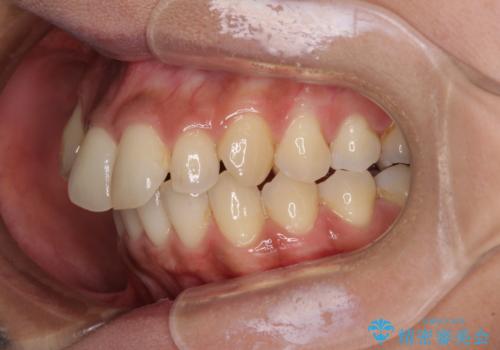

上下の正中位置が大きくずれていたため、上下正中が合わないまま終了することが予想されましたが、思っていた以上にスムーズに歯が移動し、満足いただける仕上がりとなりました。